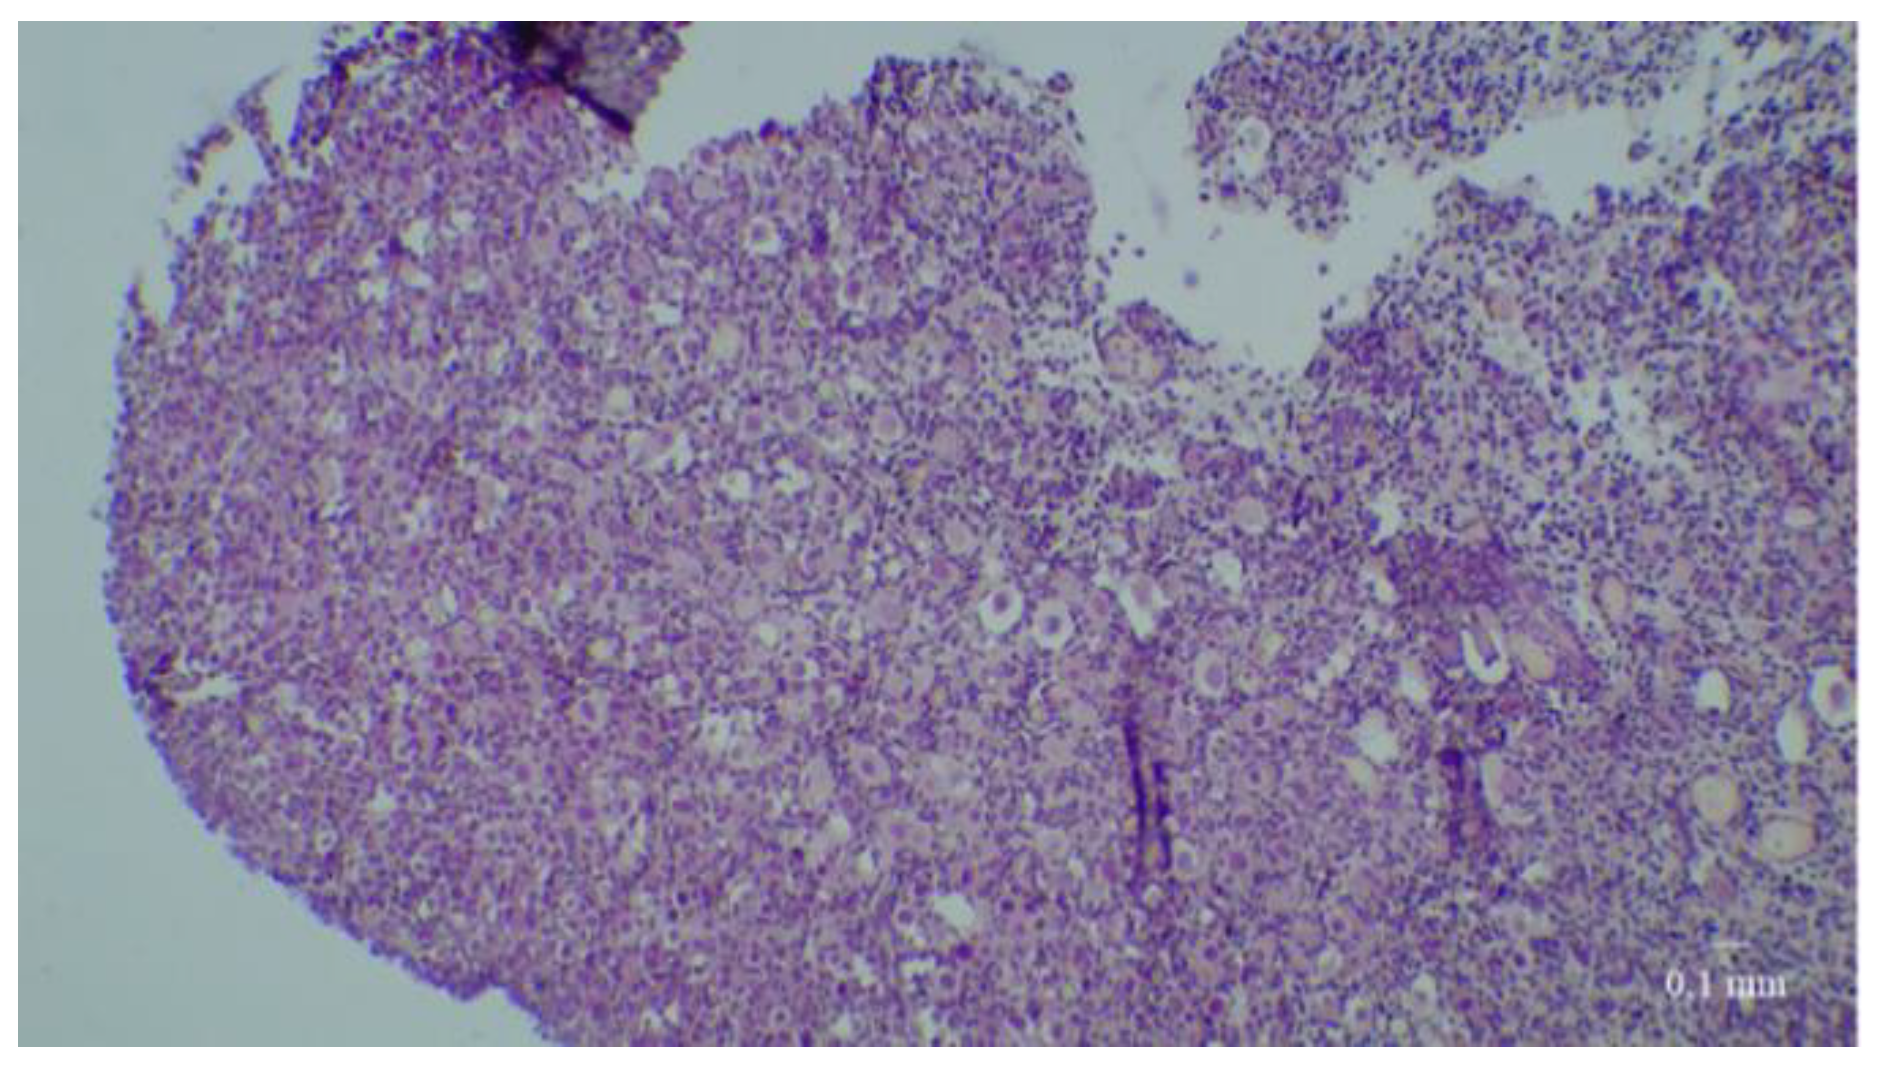

:1. Introduction

2. Materials and Methods

2.4. Histological Analyses

3. Results

3.1. Results of the First Set of Analyses with Intact Follicles as Denominator

3.2. Results of the Second Set of Analyses with All Present Follicles as Denominator